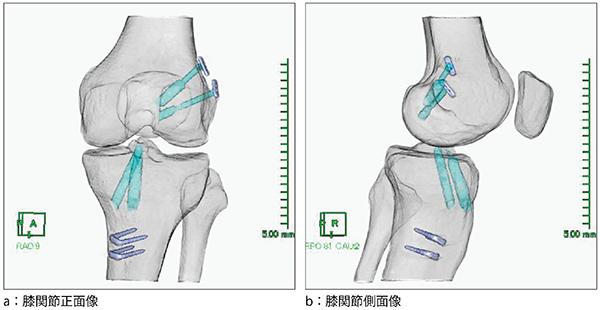

図1は,前十字靭帯再建術後の3D-CT画像である。本画像は大腿骨・下腿骨・膝蓋骨の骨表面を透かしたものに,抽出した骨孔と固定金具に色を付けマルチレイヤー表示したものである。

骨孔の描出は,WWを下げて骨と骨孔との差が明瞭になるような条件に合わせ,骨孔の走行を順に領域追加抽出する。大腿骨・下腿骨の骨表面は,もともとの骨3Dからマスクを4ボクセル縮小させた骨3Dを引き算することで得られ,オパシティを下げることで透かした3Dを作成する。骨表面を透かし,抽出した骨孔に色を付けることで骨内部の移植腱の走行が明瞭となり,患者にも理解しやすい画像となっている。

経過を追うごとに骨孔が抽出しづらくなるが,骨孔を描出する際にWW,WLを微調整し,骨と骨孔の差を可能なかぎりはっきりさせることで抽出できる。

骨孔作成位置や固定金具設置位置の術後評価では,骨内での骨孔方向まで確認できるため,手術手技の安全性や確実性の向上に寄与しており非常に有用である。

図1 前十字靭帯再建術後3D-CT